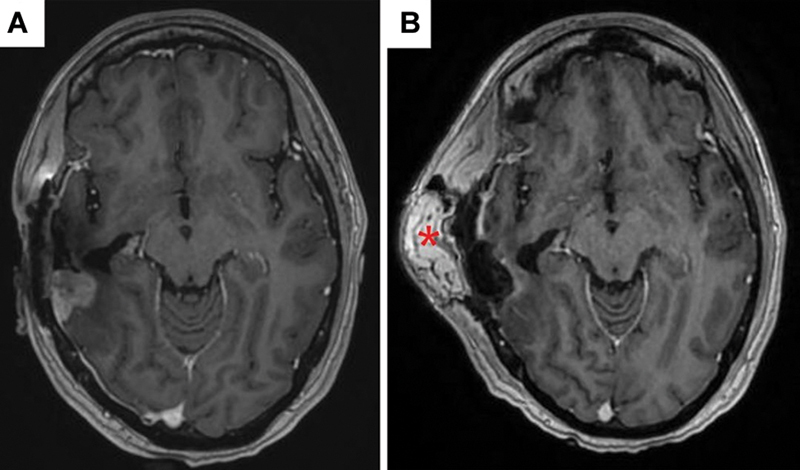

Methods: We report the case of a 37-year-old female patient with recurrent GBM and associated wound healing complications who underwent single-stage GammaTile surgically targeted radiation therapy combined with microvascular free flap scalp reconstruction.

Results: Immediate free flap reconstruction over the site of GammaTile implantation did not result in any wound healing complications and did not compromise the viability of the transplanted tissue. This approach also provided immediate and localized radiation, possibly enhancing patient progression-free survival while reducing the likelihood of radiation-induced adverse effects.

Conclusion: We report the first case of GammaTile implantation with immediate reconstruction of the overlaying soft tissue defect with a free flap. Despite the immediate local radiation produced by the tiles abutting the deep surface of the free flap, there were no complications noted in the vascularity of the transplanted tissue. This finding provides preliminary evidence supporting the safety of using free tissue transfer alongside GammaTile implantation for complex reconstruction.